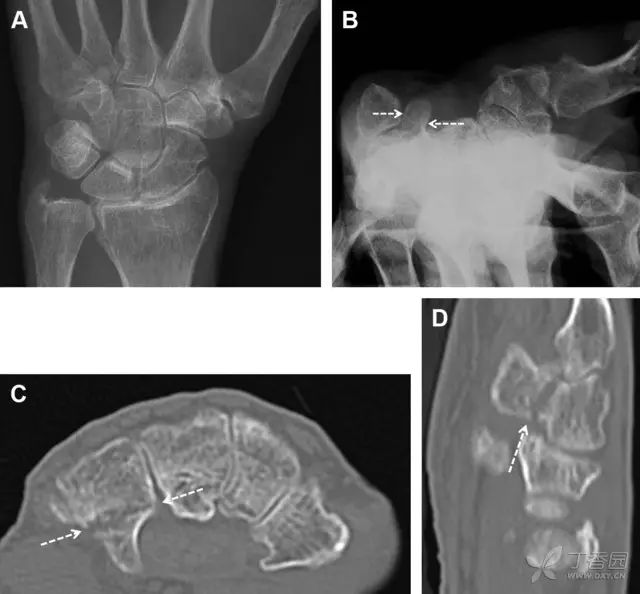

舟状骨骨折 60%~70% 发生于腰部,15% 发生于近极, 10% 发生于远极, 8% 发生于远端关节面。除了常规的前后位、侧位、斜位片外,还需要拍专门的舟状骨位片(腕关节尺偏,以舟状骨为中心的腕关节前后位片),特别是鼻烟壶有压痛时。

图 2 舟状骨骨折 (A、B)第 1 例患者,舟状骨远极关节内骨折(白色箭头),斜位片显示较清楚(B);(C、D)第 2 例患者,舟状骨腰部骨折(虚线箭头),斜位片显示较清楚(D);(E~H)第 3 例患者,舟状骨近极骨折,常规 X 线片均未看到骨折,而在舟状骨位片上才能见到骨折(虚线圆)